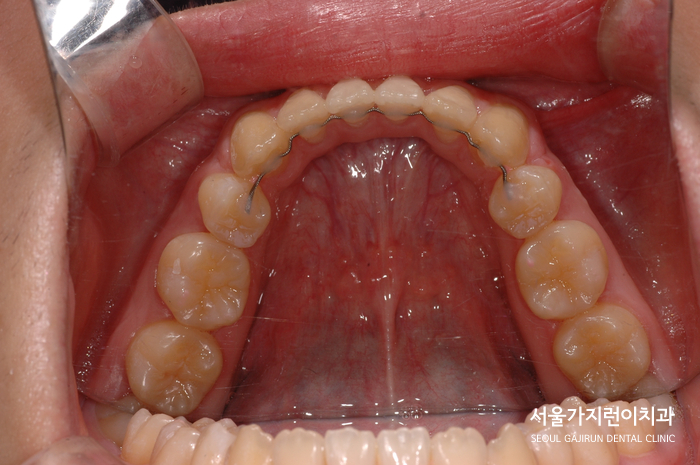

환자분의 경우 초기에는 상악 앞니를 후방으로 밀고 하악은 공간확보를 위해 정렬을 유도했는데요.

교정용 고무줄을 적절히 활용해서 치아이동을 진행했으며 이로 인해 돌출입증상도 완화된 것을 확인할 수 있었습니다. 기울어진 어금니는 바로 세워 교합을 완성했고 방향과 경사를 조금씩 바로 잡아 상하악 앞니를 서로 닿게 했는데요. 교정 이후 전체적인 치열도 가지런해진 것을 확인하여 심미성이 좋아진 사례입니다.